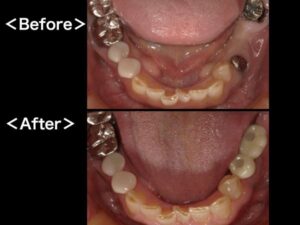

インプラントとは、顎の骨にチタン製のインプラント(人工歯根)を植立し、それを土台に上から人工歯を被せることで、歯の欠損を補う治療方法のことです。当クリニックではオペ専用の診療室を完備し、インプラント治療に力を入れております。おかげさまで数多くの治療実績を確立し、他の歯科医院様からの委託を受けてのインプラント治療も行っております。

【STEP5】人工の歯を製作・装着

型を取って人工の歯を作ります。患者様一人ひとりに合わせた形や色で製作した被せ物を取り付けます。